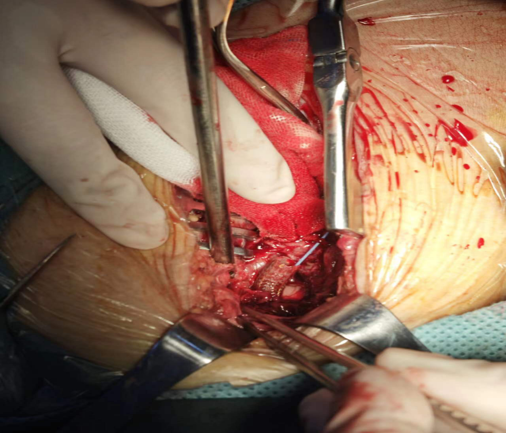

DSA下于髂分动脉叉处预置球囊阻断,大量炎性组织包裹血管,大量脓汁流出,血管破损严重,支架远端外露,向近心端探查血管,管腔感染明细

右侧腹直肌外侧切开皮肤,进入腹膜探查见髂总动脉起始端向远心端均见明显炎性改变,质脆,无法完成结扎阻断且覆膜支架与组织黏连无法取出

处理:以Hem-lock夹毕股动脉远端覆膜支架,充分止血,缝于周围组织固定,万古霉素2g撒于切口内,留置引流,vac覆盖切口。